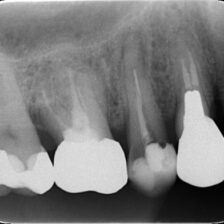

精密根管治療により、

歯を残せる可能性を最大限に

当院ではCT・マイクロスコープ・セファロなどの精密検査機器を活用し、歯を残すための選択肢をできる限りご提案します。

歯髄温存治療(MTA)や歯冠長延長術、矯正的挺出など、専門的な治療にも対応。

歯を残すための精密診断と専門治療

MTAによる歯髄温存治療に対応